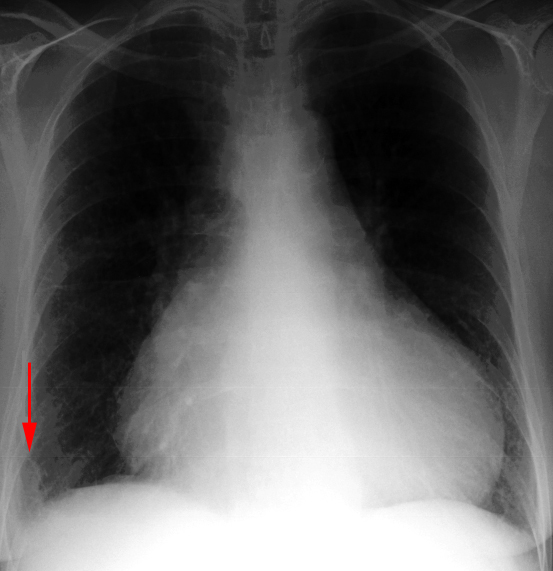

Pneumothorax in the Supine Patient

In the supine patient, intrapleural air rises anteriorly and medially, often making the diagnosis of pneumothorax difficult. The anteromedial and subpulmonary locations are the initial areas of air collection in the supine patient. An apical pneumothorax in a supine patient is a sign that a large volume of air is present. Subpulmonic pneumothorax occurs when air accumulates between the base of the lung and the diaphragm. Anterolateral air may increase the radiolucency at the costophrenic sulcus. This is called the deep sulcus sign. Other signs of subpulmonic pneumothorax include a hyperlucent upper quadrant with visualization of the superior surface of the diaphragm and visualization of the inferior vena cava.

Subpulmonary Pneumothorax

Occasionally, a posterior subpulmonary pneumothorax will result in visualization of the more superior anterior diaphragmatic surface and the inferior posterior diaphragmatic surface, resulting in the double-diaphragm sign.

Anteromedial Pneumothorax

Anteromedial pneumothoraces are differentiated into those which are superior or inferior to the pulmonary hilum. A superior anteromedial pneumothorax may result in visualization of the superior vena cava or azygos vein on the right. An inferior anteromedial pneumothorax may be evidenced by delineation of the heart border and a lucent cardiophrenic sulcus. This is the key sign of a pneumothorax as this is the highest point in the supine patient, where the air will accumulate first.